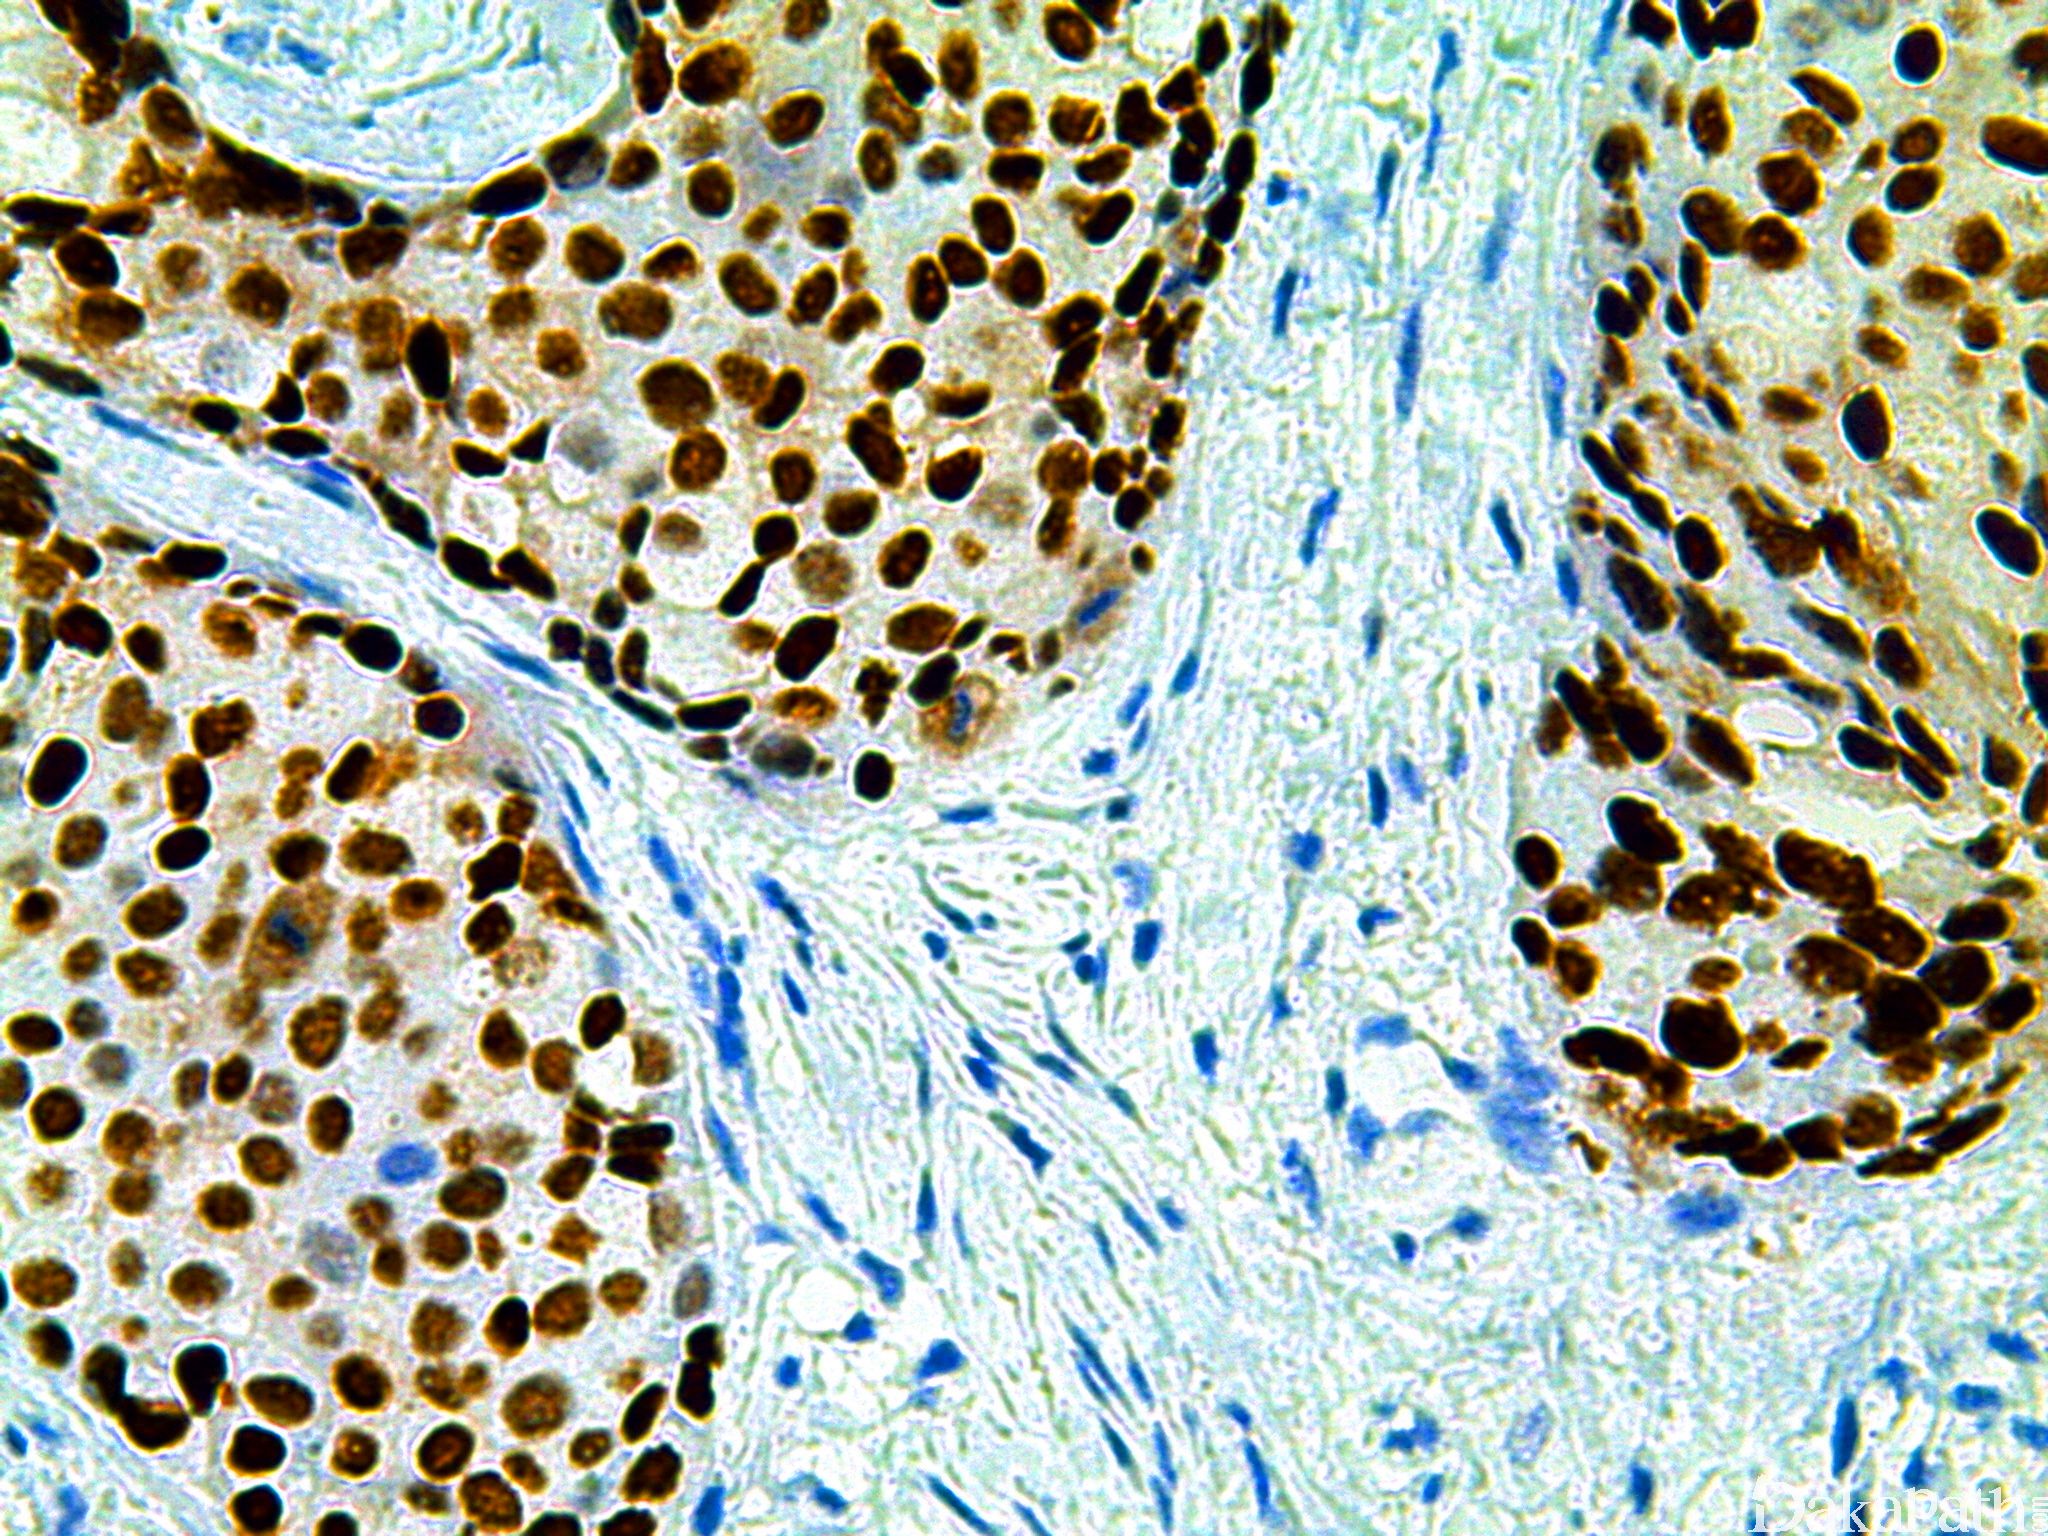

信号定位: 核着色,浆着色不计

几乎全部阳性(≥95%的病例阳性): 乳腺小管癌、乳腺乳头状癌、乳腺癌,腔 B 型、乳腺癌,腔 A 型、乳腺浸润性导管癌,伴小叶癌特征、乳腺乳头状瘤、乳头状血管内皮增生

通常阳性(<95%,≥75%的病例阳性): 血管纤维瘤,NOS、子宫内膜腺癌 I-II 级、高级别子宫内膜间质肉瘤、乳腺导管原位癌、乳腺筛状癌、乳腺浸润性癌,非特殊类型、卵巢 Brenner 瘤、卵巢浆液性癌、乳腺导管原位癌,低级别、乳腺小叶原位癌、性索间质肿瘤、乳腺浸润性小叶癌